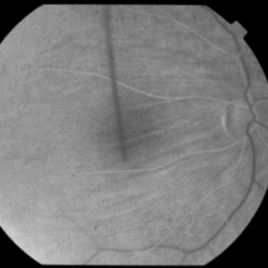

This 53-year-old man was noted to have choroidal folds right greater than left. The visual acuity was normal at 20/15. The choroidal folds are visible on OCT, especially on the vertical cuts that image across the horizontal folds. Angiography revealed staining of the folds without CNVM, choroidal mass, or optic nerve edema.

Condition/keywords: bilateral chorioretinal folds, choroidal folds